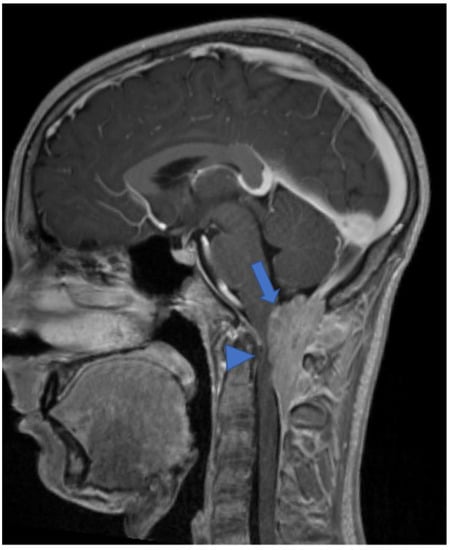

2.2. Diffuse Leptomeningeal Glioneuronal Tumor

- Gardiman, M.P.; Fassan, M.; Orvieto, E.; D’Avella, D.; Denaro, L.; Calderone, M.; Severino, M.; Scarsello, G.; Viscardi, E.; Perilongo, G. Diffuse Leptomeningeal glioneuronal tumors: A new entity? Brain Pathol. 2010, 20, 361–366. [Google Scholar] [CrossRef]

- Chiang, J.C.H.; Harreld, J.H.; Orr, B.A.; Sharma, S.; Ismail, A.; Segura, A.D.; Ellison, D.W. Low-Grade spinal glioneuronal tumors with BRAF Gene fusion and 1p deletion but without leptomeningeal dissemination. Acta Neuropathol. 2017, 134, 159–162. [Google Scholar] [CrossRef]

- Deng, M.Y.; Sill, M.; Chiang, J.; Schittenhelm, J.; Ebinger, M.; Schuhmann, M.U.; Monoranu, C.-M.; Milde, T.; Wittmann, A.; Hartmann, C.; et al. Molecularly defined diffuse leptomeningeal glioneuronal tumor (DLGNT) Comprises two subgroups with distinct clinical and genetic features. Acta Neuropathol. 2018, 136, 239–253. [Google Scholar] [CrossRef]

- Peer, S.; Murumkar, V.; Kulanthaivelu, K.; Prasad, C.; Rao, S.; Santosh, V. Diffuse Leptomeningeal glioneuronal tumor with high-grade features masquerading as tubercular meningitis—A case report. Egypt. J. Radiol. Nucl. Med. 2021, 52, 146. [Google Scholar] [CrossRef]